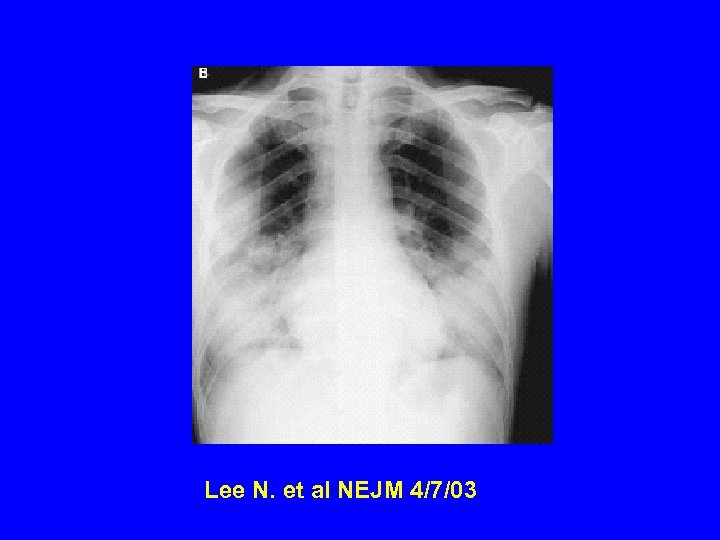

Radiology of typical case Lee NEJM 4/7/04

Radiographic Features of SARS • Infiltrates present on chest radiographs in > 80% of cases • Infiltrates – initially focal in 50 -75% – interstitial – Most progress to involve multiple lobes, bilateral involvement

Lee N. et al NEJM 4/7/03